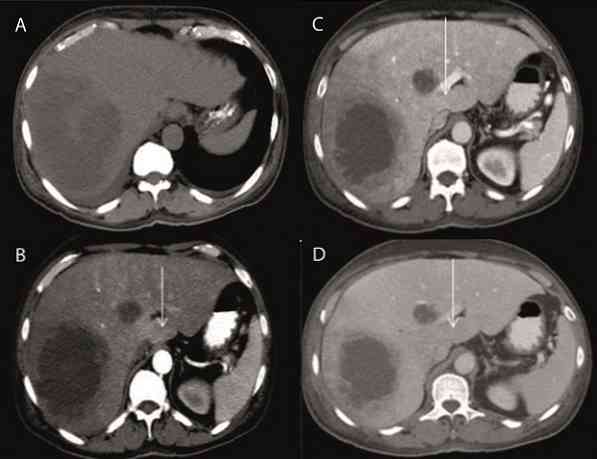

Внутричерепная гипотензия: КТ-исследования и их интерпретация

Раздел: Образы вокруг